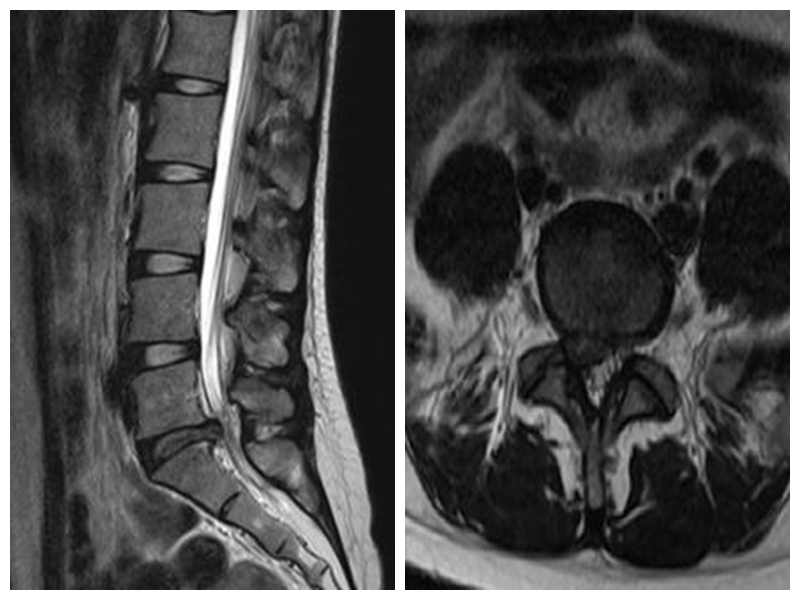

微创通道下椎间盘摘除、椎间植骨融合内固定术

此项技术手术切口小,创伤小,不需要广泛剥离肌肉及软组织。可进行髓核摘除、神经根减压、椎管减压及复位、椎弓根钉内固定、椎间融合等操作。术后恢复快,第2-3天即可佩戴腰围下地行走。平均住院时间短,并发症少,适应症广泛,可应用于治疗腰椎间盘突出症、腰椎失稳、椎管狭窄症及轻度的腰椎滑脱等疾病。

手术切口小,创伤小

典型病例:患者**,女,24岁,因“腰痛5年余,加重伴右下肢疼痛活动受限1天”平车入院。PE:右下肢直腿抬高试验10°(+),右侧踝反射消失,右下肢胫前肌、小腿三头肌肌力4级,右砪长伸肌力4级,左下肢肌力5级。右臀部、右大腿后侧针刺有麻木感,鞍区皮肤感觉正常。

本例患者术后3天在腰围保护下独立下地行走,腰痛及右下肢麻痛明显缓解。